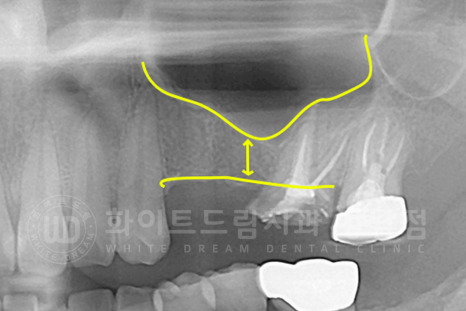

3D-CT를 이용하여 확인하니 잇몸뼈의 두께가 임플란트를 식립하기에는 많이 모자란 상태였기에

상악동 거상술(Lateral)을 진행하기로 했습니다.

▲ 6개월의 회복 기간 후 보철 제작에 들어갔고 최종 보철 세팅 후 x-ray입니다.

수술 전과 후의 잇몸뼈 두께를 보면 차이점이 한눈에 확인되실 겁니다. ^^

동일 인물이며, 동일 환경에서 촬영되었습니다.